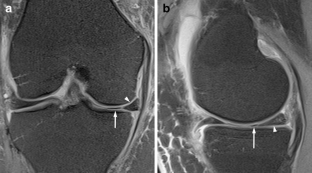

A total of 914 consecutive exams from 875 patients (524 men; mean age, 35 years) were reviewed. Vacuum phenomenon was found in 12 patients (prevalence 1.3%). In six (50%) patients, VP mimicked a meniscal tear, with four cases simulating a torn medial discoid meniscus. The VP signal was not easily differentiated from meniscal signal on most sequences in most cases (9/12). Gradient-recalled echo (GRE) localizer images proved most definitive, with 3D SPACE images the next most effective. Fast spin echo (FSE) images were only occasionally able to differentiate VP from meniscus.

Rarely recognized on MR, VP can mimic meniscal pathology, potentially leading to inappropriate surgery. Because differentiation of VP from the meniscus is challenging on FSE at 3 T, radiologists should become familiar with the appearance of VP and review GRE localizer or 3D images carefully to avoid misinterpretation.